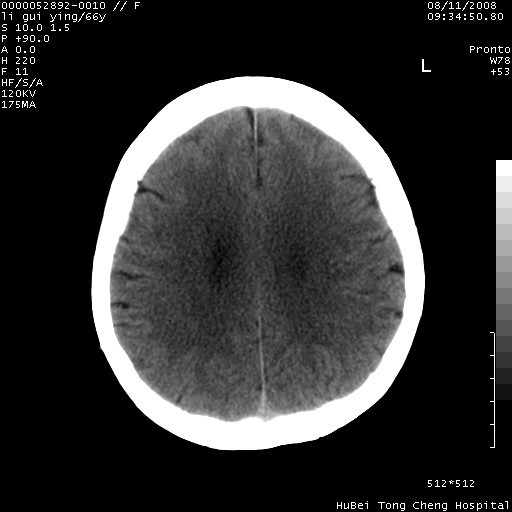

以下是引用yangyudong333在2008-8-12 12:22:00的发言:[br]1.病灶呈圆形[br]2.周围无水肿带[br]3.密度不均匀,内有点状钙化[br]4.无占位效应[br] 考虑良性占位性病变,血管瘤可能性大